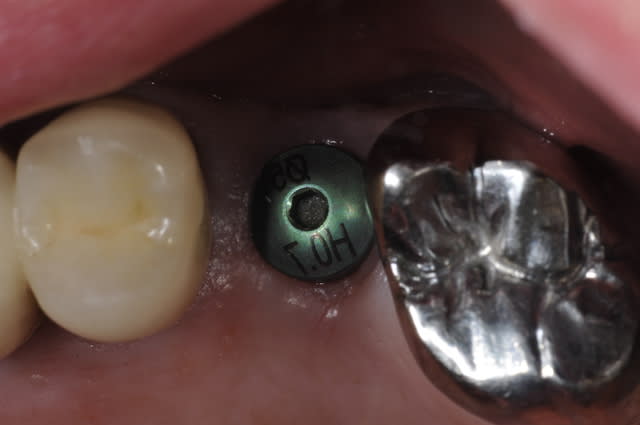

J'ai un patient qui se présente au cabinet avec un implant TEKKA en bouche.

- implant : je pense que c'est un "Krestal"

- diamètre : je suis par contre plus dans le flou car la vis de cicat est gravé indiquant un diamètre de 5 mais impossible de rentrer le transfert ce matin... De plus la vis de cicat est verte (qui ne correspond pas au diamètre de 5 couleur violet) bref je suis perdu.

c'est un inkone

Ca ressemble à un In Kone

De mémoire, dans le système Inkone, le pilier de cicatrisation vert veut dire : hauteur 0,7 mm.

Je confirme ce système est à poser en sous crestal.

J'ai observé ce type de cratérisation avec des piliers prothétiques de hauteur 1,5 mm (jaunes), je n'ai jamais utilisé les 0,7 mm de haut.

Pour moi quand la hauteur gingivale le permet je préfère utiliser les piliers hauteur 3 mm (violets). J'ai observé moins de perte osseuse dans ce cas.

Surtout qu'un pilier de hauteur faible (1.5 ou pire 0.7) aura probablement été utilisé ici en gros diamètre pour créer ce cratère.

Si on enfoui l'implant, un avantage est de préparer le profil d'émergence depuis la profondeur, avec un pilier peu large et haut (ex: diam. 4, htr 3).

Pilier large et bas = compression tissulaire = cratère.

Effectivement, pas dit que ce soit prioritairement infectieux. Peut-être stabilisable, voire reconstructible. Bonne idée de mettre sous pro un temps. Mais vire les piliers inférieurs à 1.5 (idéal 3 quitte à retailler), et si 1.5 (jaune), pas large.